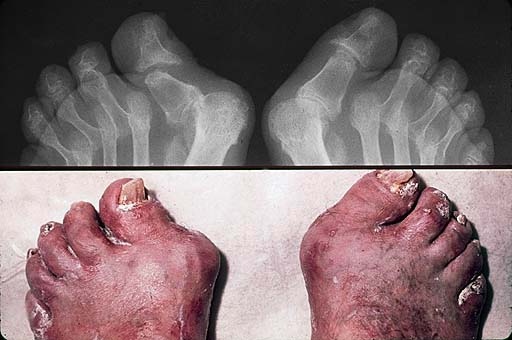

Psoriatic arthritis is similar to three other forms of arthritis which

may occur with psoriasis: rheumatoid, gout, and Reiter's syndrome. The diagnosis

of psoriatic arthritis is made on the basis of a medical history and physical

examination, blood studies, and x-rays of the joints that have symptoms.

Arthritis Mutilans

This is a severe, deforming and destructive arthritis which affects less than five percent of people with psoriatic arthritis. It principally affects the small joints of the hands and feet, although there is frequently associated neck or lower back pain. This type can progress over months and years. Arthritic flares and remissions tend to coincide with skin flares and remissions.